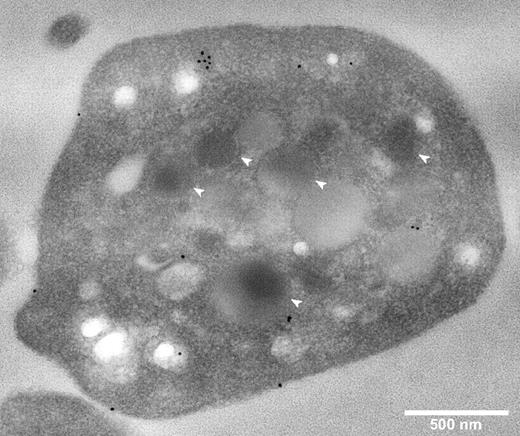

The intracellular localization of CFH in fixed permeabilized platelets was determined by immunostaining and imaging of sections via transmission electron microscopy (TEM), and of whole cells by laser fluorescence spinning disk confocal microscopy. TEM of immunogold-labeled sections (Figure 2) showed CFH-labeled protein distributed around the cell surface and throughout the cytoplasm, with no evident specific association with α-granules or other organelles. A rabbit polyclonal anti–human CFH (SCRs19-20) antibody was used for these experiments and those described in Figure 3; an antibody specific for CFH (SCRs1-4) recognizing the N-terminal region gave the same results (data not shown).

Platelet CFH is distributed throughout the cell and not preferentially localized to α-granules. Thin-section TEMs of representative normal platelets immunogold labeled for CFH (original magnification ×40 000). White bar represents 500 nm; white arrows, α-granules. Primary anti-CFH rabbit polyclonal antibody was detected by immunogold-tagged (10 nm) secondary antibody (black spots). Immunogold-CFH was distributed throughout the cytoplasm with some on the surface but none in recognizable α-granules (compare white arrows with black spots).

The whole-cell distribution of CFH was examined in fixed, permeabilized platelets costained for CFH and other proteins having known intracellular distributions (Figures 3–4). Cells in an unperturbed, resting state were examined as illustrated in Figure 3A where β-actin staining outlines the plate-like shape of cells viewed from the top and side, and Figure 3B where tubulin rings (red) delineate quiescent platelets with intact VWF-containing α-granules (green). These granules were consistent in size and distribution with published images.23 Because previous reports suggested that CFH is localized to platelet α-granules, we first assessed its distribution relative to the known granule-associated proteins VWF (Figure 3C) and fibrinogen (Figure 3D), which are present in 2 distinct populations of α-granules,23 CD63 (Figure 4A), which is present in both dense (δ-) granules and lysosomes, and the lysosomal protein LAMP-1 (Figure 4B). The results show that, unlike these proteins, CFH is not concentrated in granules but rather appears to be present throughout the cytoplasm and possibly on the cell surface (as seen in TEM images; Figure 2). The presence of CFH in these locations is supported by the overlap observed in cells costained for CD61 (GPIIIa, β3 integrin; Figure 4C), found on the cell surface and in the cytoplasm, and the cytoplasmic protein β-actin (Figure 4D). Unpermeabilized platelets showed markedly less CFH staining (data not shown), indicating that much of the protein is inside (washed) cells. These visual impressions were confirmed by the results of whole-cell protein colocalization analysis of representative images (Table 1). Mean values obtained for the Pearson correlation coefficient indicate significant colocalization of CFH with β-actin and CD61, but not with vesicle-associated proteins. The values obtained for the Manders overlap coefficient confirm the strong colocalization of CFH with β-actin and a weaker association with CD61 (for which the value of the overlap coefficient falls below the arbitrary significance limit of 0.7),24 which is nevertheless stronger than the association with any of the other proteins examined. Taken together, both TEM and laser fluorescence confocal microscopy studies indicated that CFH is distributed throughout platelets and to some extent on the cell surface, and is not concentrated in or confined to α-granules or other secretory vesicles.

It has been proposed that CFH is stored in and released from platelet α-granules,19,38 which suggests that CFH is expressed within the platelet lineage by precursor megakaryocytes and/or taken up from plasma. We began our examination of these possibilities by analyzing the protein content of megakaryocytes grown in serum-free suspension culture, normal, and ARC syndrome platelets (Figure 1). We found that, although some platelet CFH appears to originate from endogenous synthesis in megakaryocytes, α-granules are not required for its presence. Direct examination via TEM of CFH in immunogold-labeled sections from normal human platelets (Figure 2) showed CFH distributed on the cell surface and throughout the cytoplasm, with some apparent association with cell membranes but not specifically with α-granules or other recognizable vesicles.

Surprisingly, the most abundant colocalization of CFH was with β-actin (Figure 4D; Table 1). Although this is consistent with the TEM observations showing a nongranular cytoplasmic distribution within platelets (Figure 2), this was somewhat unexpected because platelet CFH has been reported to be released from agonist-stimulated platelets.19 We have also observed release of CFH from platelets stimulated with a variety of agonists (data not shown), indicating that, in addition to granule-dependent secretion, platelets may also be capable of releasing significant amounts of surface-associated and/or cytoplasmic proteins.